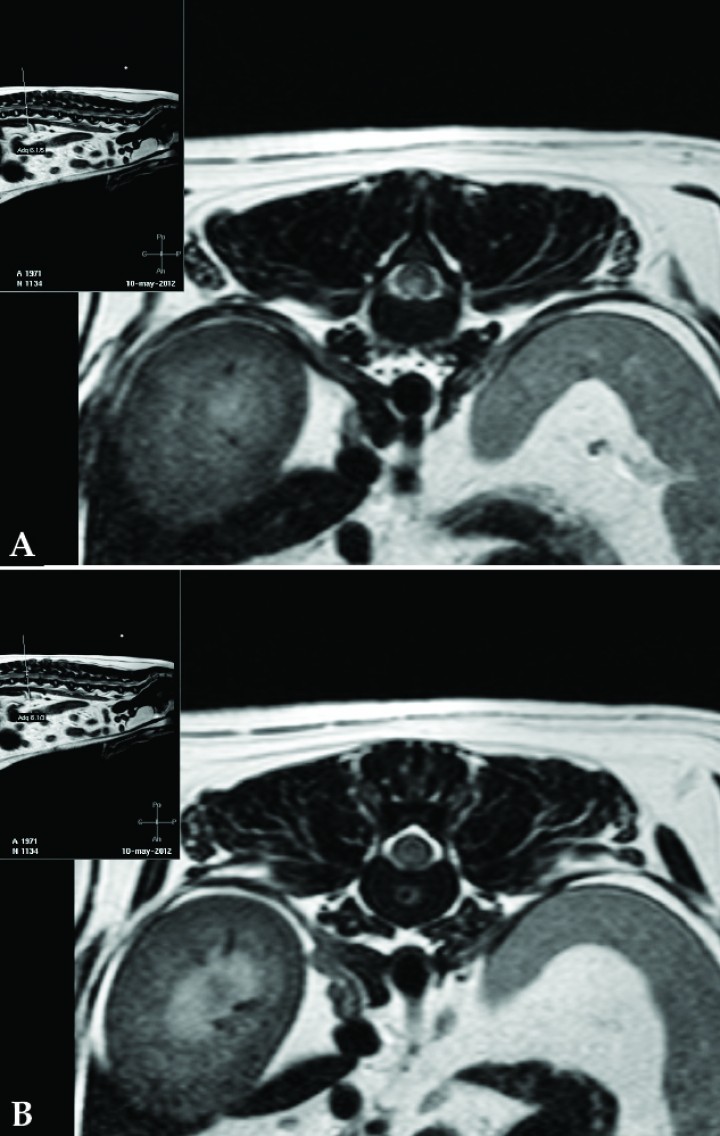

Dado el examen físico general normal y la ausencia de antecedentes clínicos y de alteraciones en el hemograma, la bioquímica sanguínea y las radiografías de tórax se consideró conveniente realizar, bajo anestesia general inhalatoria, un estudio por RM de alto campo (Philips Intera 1.5T, Holanda) de la columna torácica y lumbar. En este estudio se evidenció una alteración de la señal intramedular localizada en el nivel correspondiente al tercio caudal de la vértebra T13, con mayor afectación derecha, caracterizada por prolongación de los tiempos de relajación (hiperintesidad en secuencias ponderadas en T2 e hipointensidad en T1) de límites relativamente definidos y ausencia de captación de contraste (Fig. 1A). El disco intervertebral T13-L1 presentaba en su núcleo pulposo una zona hipointensa, con halo hiperintenso en secuencias ponderadas en T2 (Fig. 1B). El diagnóstico presuntivo más probable fue mielopatía isquémica, probablemente por embolismo fibrocartilaginoso de material de núcleo pulposo proveniente del disco T13-L1, sin poder descartar por completo extrusión aguda no compresiva.

<p>Imágenes de Resonancia Magnética. (<strong>A</strong>) Corte transversal sobre el tercio caudal de T13, imagen ponderada en T2. Se observa una alteración de señal intramedular hiperintensa, de límites definidos, algo lateralizada a la derecha. (<strong>B</strong>) Corte transversal sobre el disco intervertebral T13-L1, imagen ponderada en T2. En el núcleo pulposo se observa una disminución de señal focal rodeada de un halo hiperintenso.</p>

Imágenes de Resonancia Magnética. (A) Corte transversal sobre el tercio caudal de T13, imagen ponderada en T2. Se observa una alteración de señal intramedular hiperintensa, de límites definidos, algo lateralizada a la derecha. (B) Corte transversal sobre el disco intervertebral T13-L1, imagen ponderada en T2. En el núcleo pulposo se observa una disminución de señal focal rodeada de un halo hiperintenso.